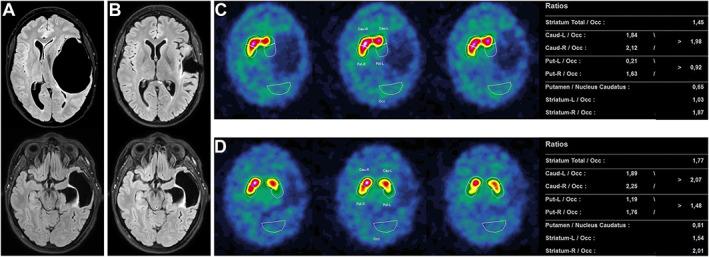

Successful Surgical Treatment of an Intracranial Arachnoid Cyst Inducing Holmes' Tremor.

Aubignat Mickael, Tir Mélissa, Vandici Ovidiu-Florian, Lefranc Michel

Department of Neurology Amiens University Hospital Amiens France.

Department of Nuclear Medicine Amiens University Hospital Amiens France.

Mov Disord Clin Pract. 2023 Apr 17;10(6):998-1000. doi: 10.1002/mdc3.13744. eCollection 2023 Jun.